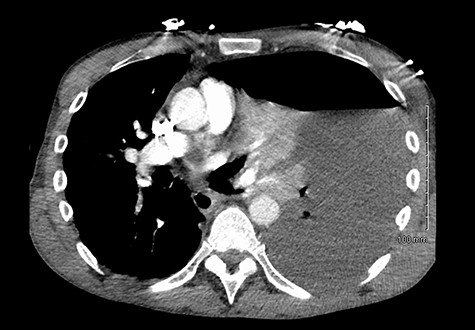

He maintained a high daily chest drain output of between 2.5 and 5 l. Upon recommencement of enteral feeding on day 3, we noticed an increase in opacity of the drainage fluid (Fig. 3). Normal triglyceride and chylomicron levels ruled out a chylothorax. Cultures from the drain eventually grew Enterococcus faecium, Candida albicans and Escherichia coli consistent with gut flora. At this point, an aerodigestive fistula was suspected. This was confirmed by a dye test subsequently performed with green ice cream, which tainted the drainage fluid green (Fig. 4). A repeat CT scan with oral and intravenous contrast delineated a fistula between the greater curvature of the stomach and the left basal pleura, with an extensive empyema (Fig. 5).

(Left) Contrast in stomach and pleural fluid are iso-dense confirming a fistula; (Right) neck of hernia in the diaphragm.